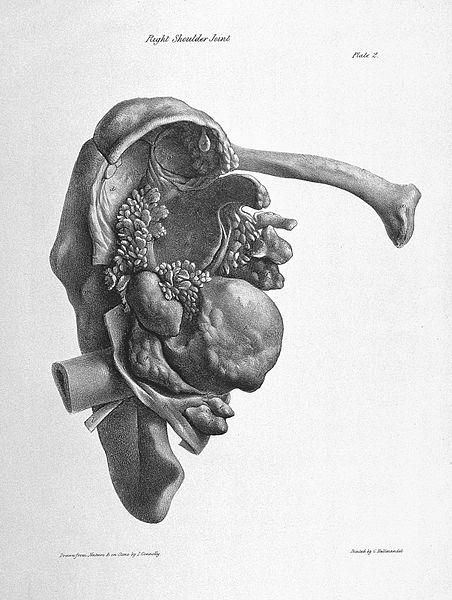

Arthritic changes – Arthritis is related to a condition of painful joints due to inflammation or swelling. A type of arthritis is rheumatoid arthritis, it is an autoimmune disease where the immune system attacks the joints, starting with the lining of joints. Rheumatoid arthritis is heavily related to lung problems, about 80% of arthritic patients have lung-related issues, making it the second leading cause of death with rheumatoid arthritis patients. Rheumatoid arthritis caused lung problems are most commonly extra-articular i.e., outside of the joints and involves pulmonary nodules; damage to the lung airways, pleural effusion and interstitial lung disease. In rheumatoid arthritis associated interstitial lung disease the auto-immune system gets over active and attacks the lungs and causes scarring. With time, the scarring build-up leads to difficulty breathing and reduced lung function.